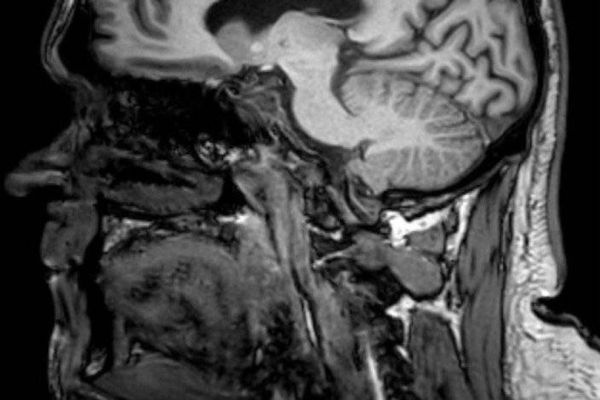

However, when the father-of-two experienced a seizure while driving two years later - losing consciousness and crashing his van - a CT scan uncovered a glioblastoma. Glioblastoma is an aggressive and incurable type of brain cancer, and Jamie was told he had seven months to live.

Jamie was transported to Chesterfield Royal Hospital where medics performed CT scans. At first, they were believed to show a bleed caused by the impact of his crash but further examination revealed something more serious.

Jamie was referred to Royal Hallamshire Hospital in Sheffield, where he met with a surgeon who identified a mass on his brain that needed urgent surgery. He underwent a craniotomy to remove all the visible tumour but the operation left Jamie relearning how to walk and talk.